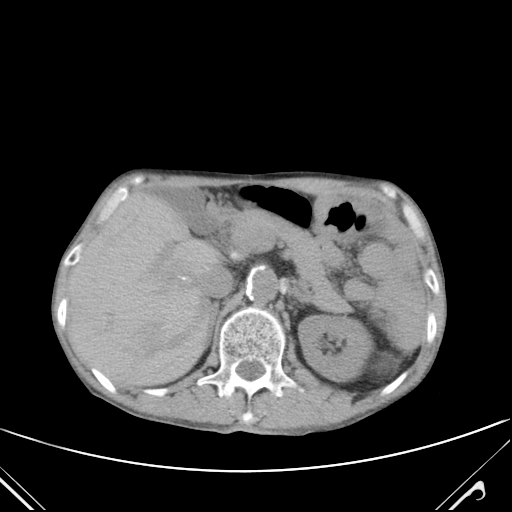

影像2025